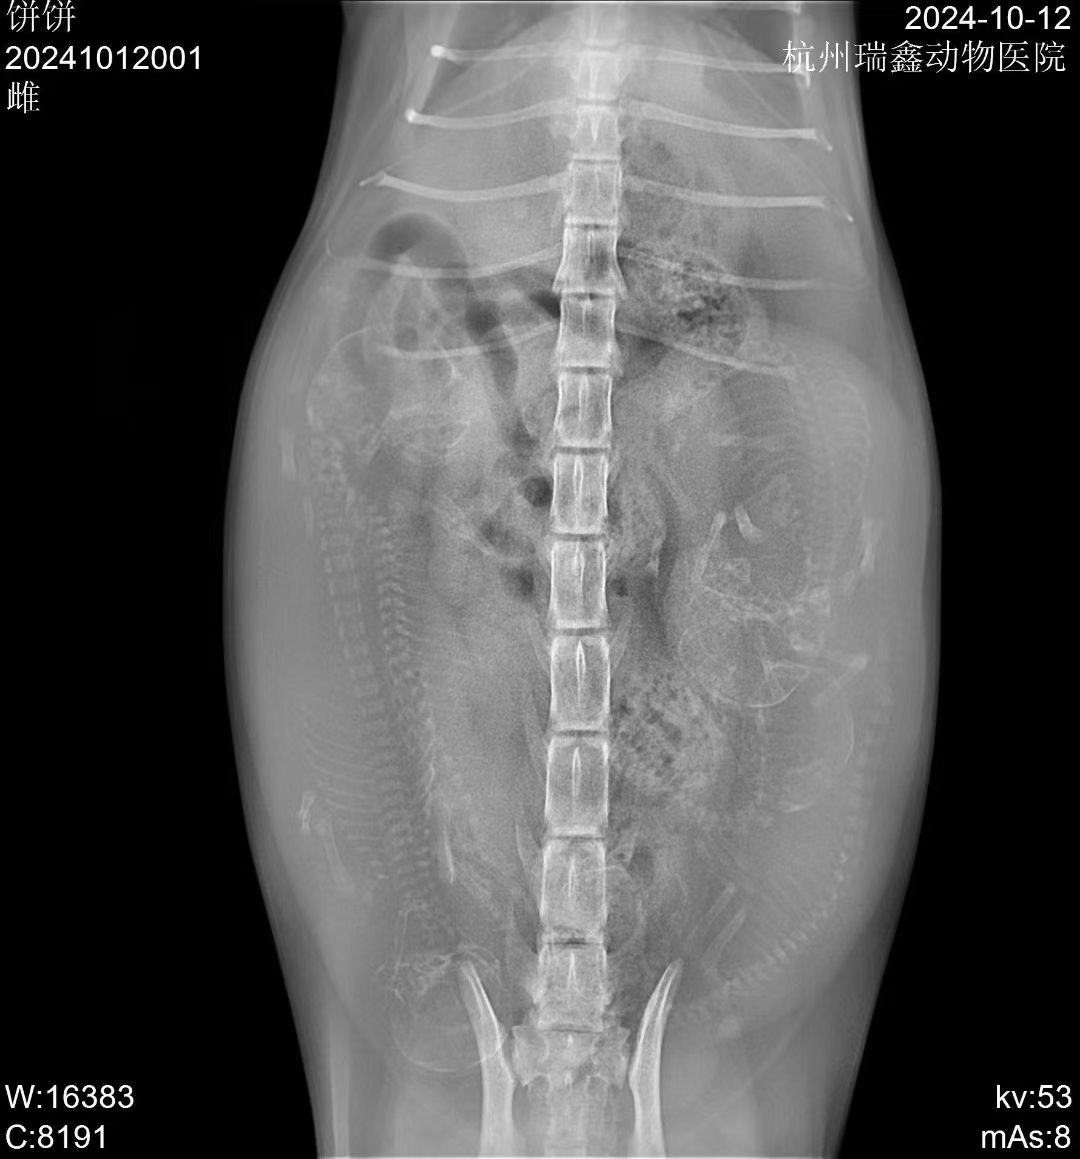

前几天的一个咨询 💬

铲屎官说猫咪一岁多,刚养了两个月

症状描述:​腹部隆起,呼吸急促,看了视频有点腹式呼吸,建议抓紧拍个片子🔍

——原来这是怀了啊,喜提小猪咪五只 😄